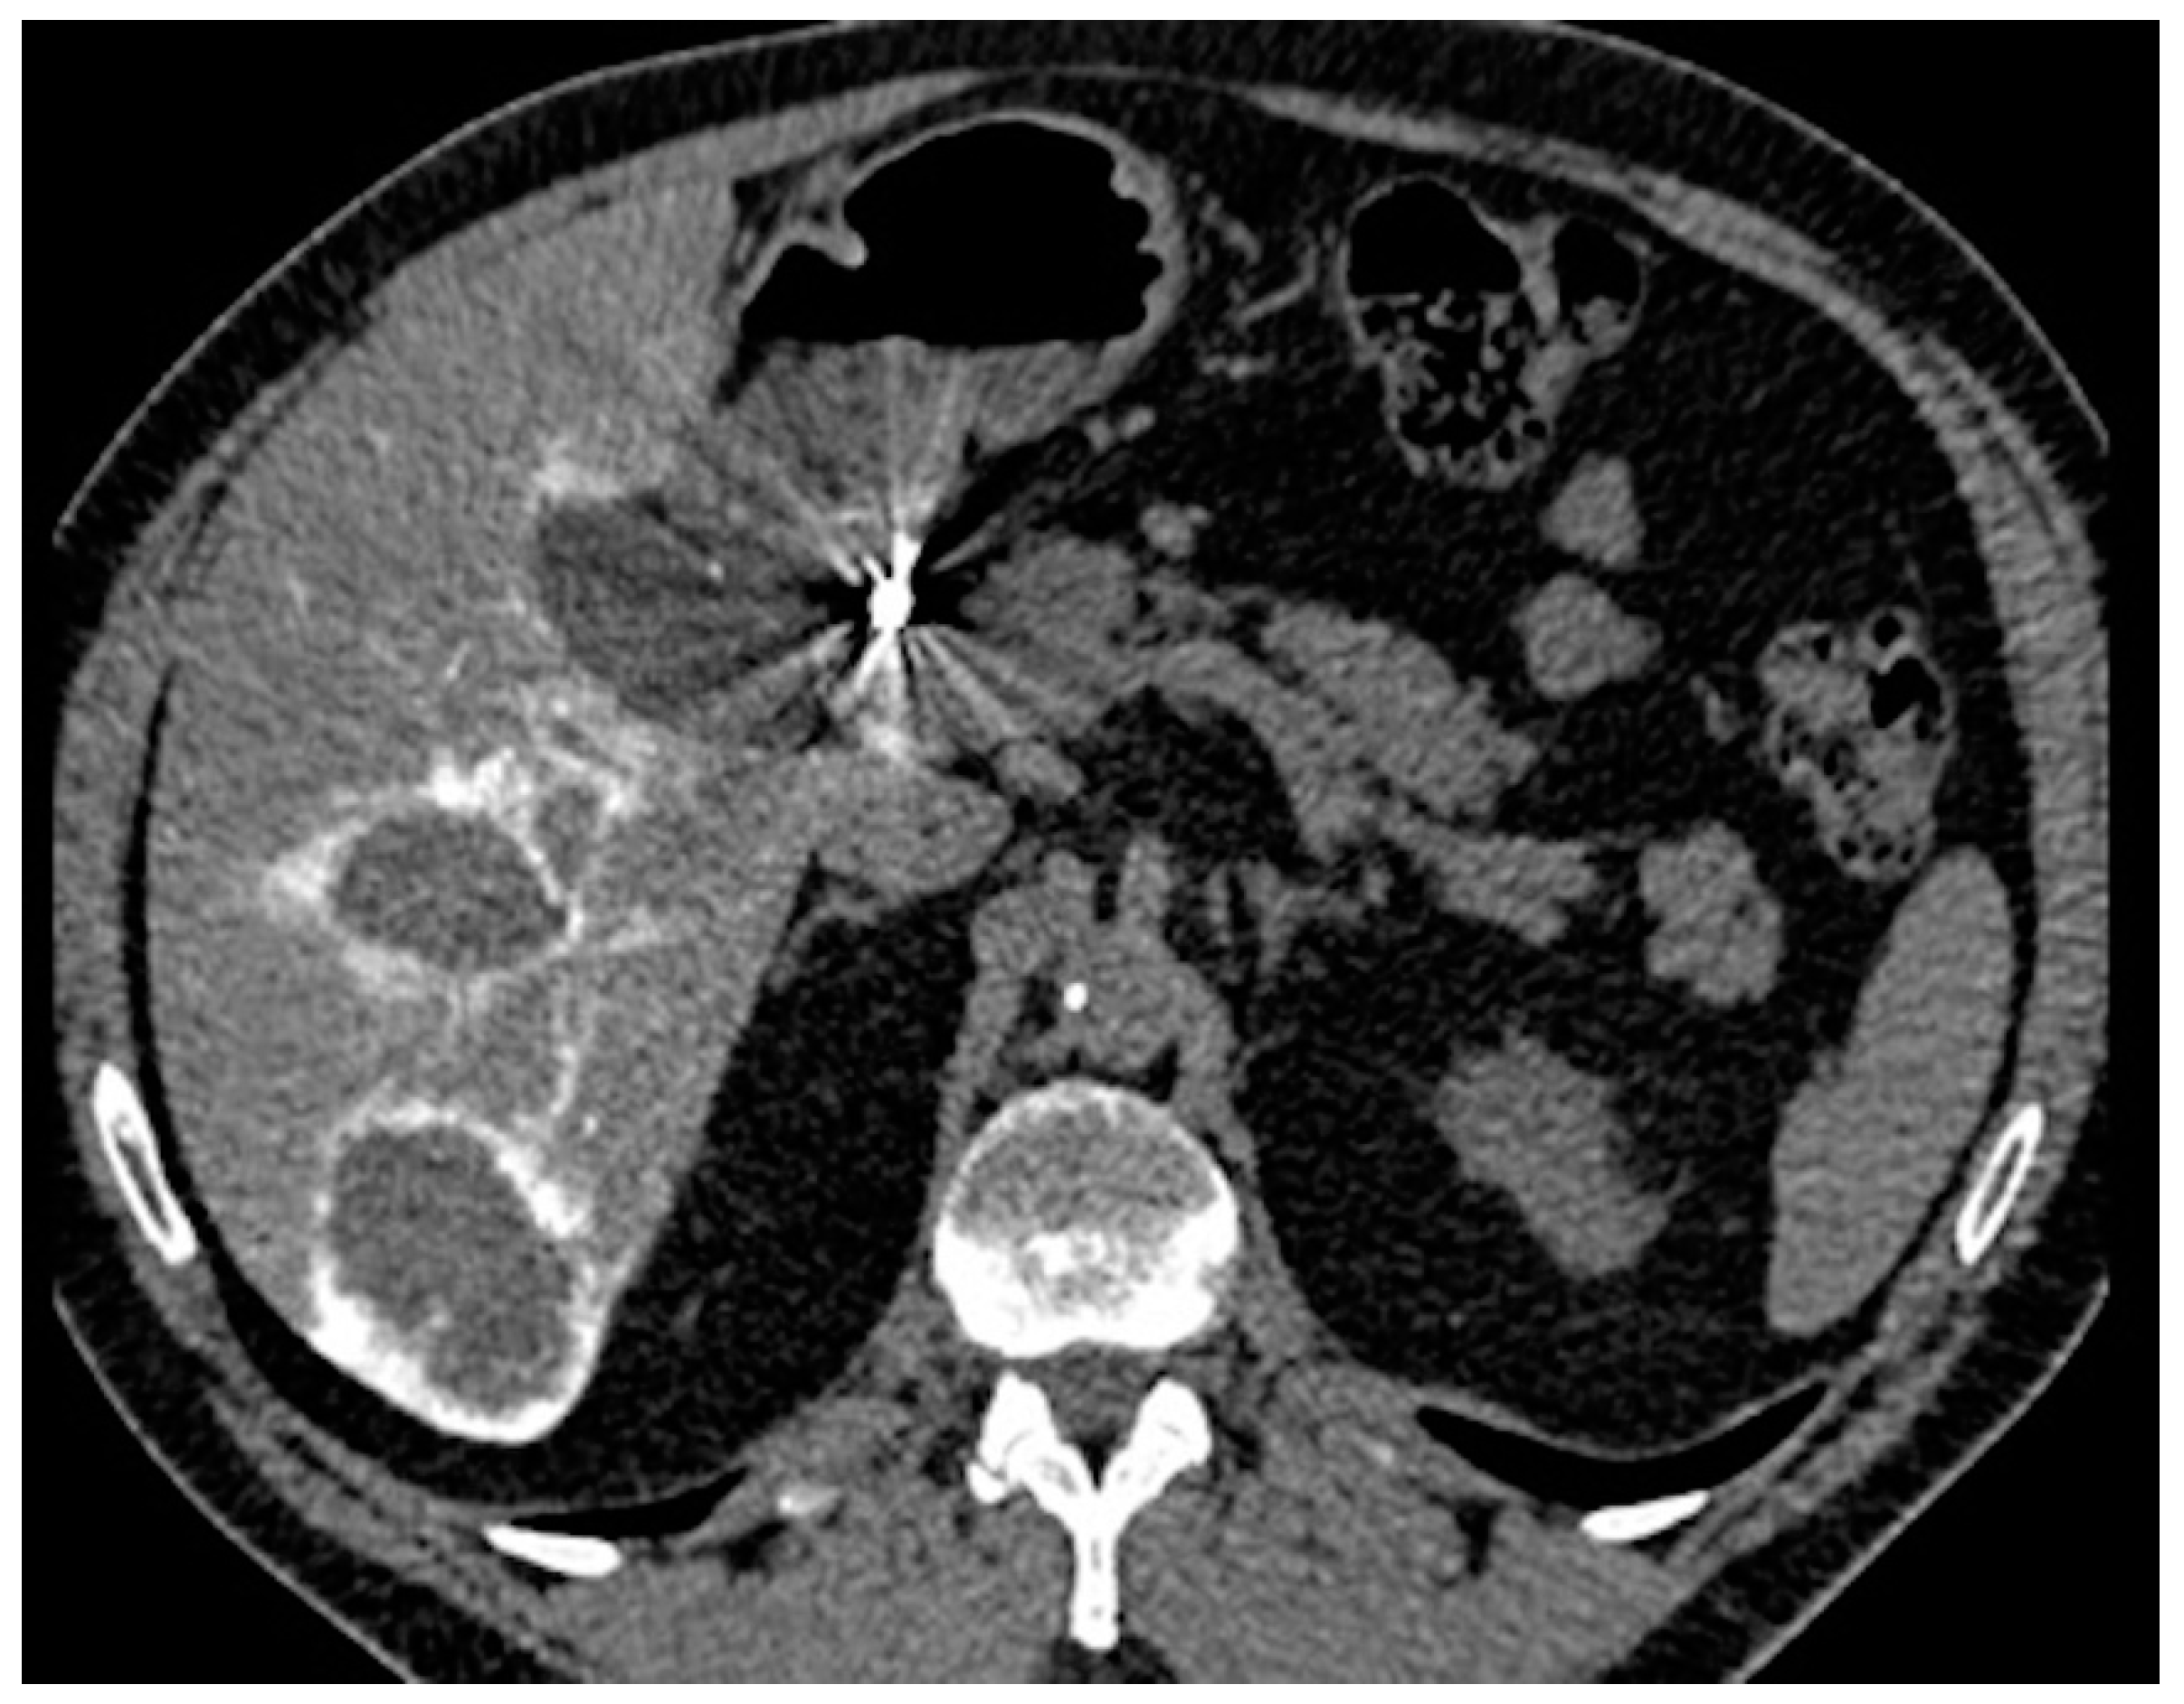

Percutaneous Implantation of a Microcatheter-Port System for Hepatic Arterial Infusion Chemotherapy of Unresectable Liver Tumors: Technical Feasibility, Functionality, and Complications

2.2. Percutaneous Microcatheter-Port System Implantation